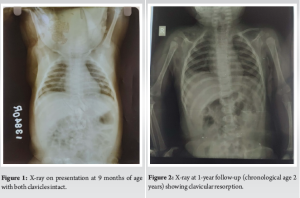

A 9-month-old infant presented to us with high-grade fever and pain in the region of the medial end of right clavicle (Fig. 1). Clinical examination revealed tenderness, swelling and discharging sinus over medial end of clavicle. Serological parameters and magnetic resonance imaging (MRI) were suggestive of medial clavicular osteomyelitis. The patient was operated on with incision, drainage of pus and wide local debridement for the osteomyelitis, and pus was sent for culture. The patient was given sensitive antibiotics for 6 weeks and the patient was kept on regular follow-up. There was complete resolution of infection at 6-week follow-up with no evidence of recurrence. The wound healed uneventfully and there was no clinical or serological evidence of infection. At sequential follow-ups of 1 and 5 years clavicle was not visualized (Fig. 2-4). At the latest 13-year follow-up, the patient has no evidence of right clavicle bone in comparison to the complete normal left clavicle (Fig. 5; 6a and b). But upon detailed clinical evaluation, the patient has no functional deficit (Fig. 7 and 8). He is able to attend school and carry out all his daily activities without any trouble whatsoever. Manual muscle testing grading showed near-normal power in all the muscle groups of the right upper limb. The DASH score in the right limb was 10 signifying better function. The grip strength of the right hand was not reduced as compared to the opposite normal side.

Hematogenous osteomyelitis of the clavicle is a rare entity with the incidence being around 1–3% [6,7]. Owing to the similarity of the clavicle to other membranous bones like ilium, osteomyelitis of clavicle is more difficult to treat than osteomyelitis of long bones [8]. The primary aim of management remains early diagnosis and prompt management with wide local debridement and appropriate sensitive intravenous antibiotics [1,9]. The known complications of clavicular osteomyelitis are sepsis, mediastinitis and hemorrhage from great vessels [10]. A rare and sparsely reported complication of osteomyelitis remains resorption of the bone. Bacterial infection of bone causes inflammatory bone loss that results from an imbalance between the increased activity of bone-resorbing osteoclasts, and a decrease in bone-forming osteoblasts [11]. In our case, it was noted at sequential follow-ups that the clavicle had not grown as much as the opposite side. There was definitive evidence of clavicular resorption at 1- and 5-year follow-ups. At sequential follow–up, the patient had no complaints of functional deficit. At final 13-year follow-up, we decided to go for a detailed evaluation of the status of the upper limb. Clinical examination revealed no functional deficit whatsoever. The patient has no difficulties in performing all the activities of daily living. He is able to attend school and play merrily. Objective evaluation with DASH score was around 10 pts (Range 0–150 with 0 being best function and 150 being poor function) and the grip strength by dynamometer showed no significant difference as compared to the normal opposite side. Upon imaging the X-ray, computed tomography and MRI revealed complete clavicular resorption. In this particular case, the patient has no clavicle at all! Yet he is able to perform all his activities smoothly and without any deficit.